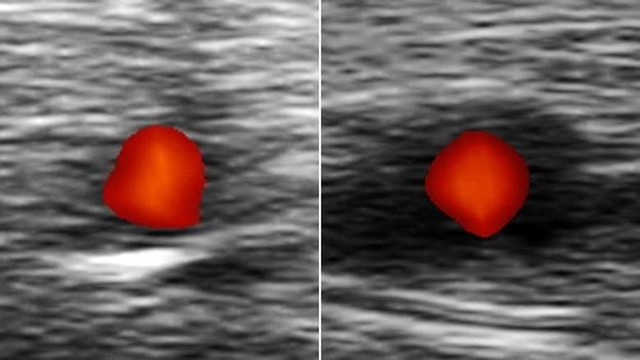

Se o paciente estiver sob risco, ele é imediatamente examinado por ultrassom - se o paciente tiver a arterite temporal, o exame revelará uma faixa preta, uma "auréola negra", ao redor da artéria temporal.

Este sistema de resposta rápida, acabou salvando a visão de Roger Keay. "O médico reconheceu a condição imediatamente. Fez um teste de ultrassom e me mostrou na tela. Salvou a minha vista. Eu sou um homem de sorte. Se eu tivesse 1 milhão de libras daria a ele", disse Keay.